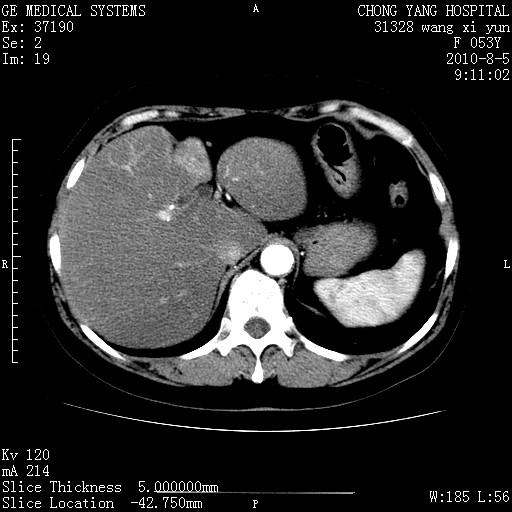

标题: CT28214:F41Y 血尿二十天,建议盆腔平扫加增强。

1)考虑肝左叶胆管细胞癌。2)脂肪肝。